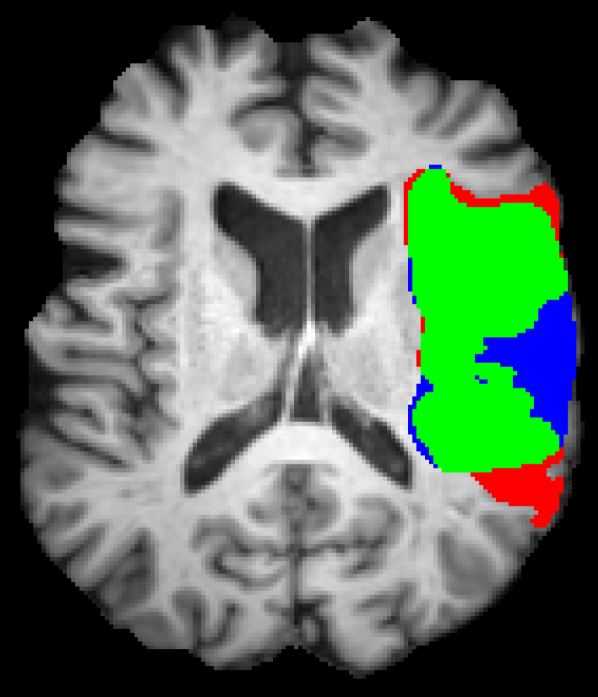

Representative examples of the qualitative results from the proposed method can be found in Figure 4. Cases 9 and 15 represent the overall results of the proposed methodology, correctly detecting the lesions in most cases with an outline that approximates the provided gold standard. Among the observed limitations are inaccurate borders and over/under segmentation of certain regions. For instance, in case 5 the lesion was undersegmented due to a heterogeneous appearance of the gold standard lesion while in case 13 two false positive lesions are detected due to the previous existence of chronic stroke lesions with a similar appearance.

Refer to caption

(a) Case 5

(b) Case 9

(c) Case 13

(d) Case 15

Figure 4: Output segmentation masks of representative cases from the training images of ISLES 2015 SISS dataset. On all images, true positives are denoted in green, false positives in red and false negatives in blue.